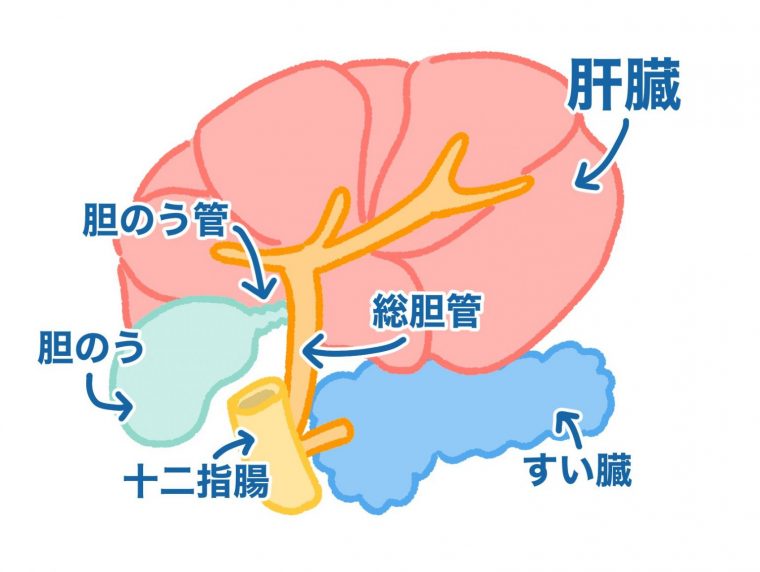

犬 胆泥症 原因-胆泥 をかたちづくっているのは コレステロール や 黄疸色素 ( ビリルビン )、 カルシウム などの微細な 結晶 が 胆嚢壁 から分泌される 粘液 に包まれたものと考えられますが、他にも 炎症 によっこんにちは。獣医師の清水いと世です。 今回は、わんちゃんの胆泥症について説明します。 前編は、胆泥症の原因や検査方法や症状について、後編は治療や予防方法について説明します。 犬の胆泥

胆泥症・胆石症について 胆嚢は、胆汁を産生し貯留する器官です。 胆汁には、脂肪を分解し水に溶けやすい状態に(乳化)する役割を持っています。 胆嚢に貯えられた胆汁は、元々サラサラの水胆泥を生じさせた原因や疑われる原因があれば、それを取り除きます。 そのために、 犬の胆泥症 <前編> で説明した原因追及のための検査結果が重要になります。 肝臓の異常が認められるので